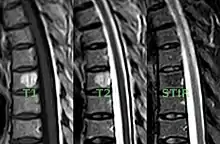

MRI

Baudrez, Galant, and VandeBerg found that MRI appearance is dictated by histology of the tumor-like lesion—Vascularity, interstitial edema, and interspersed fat.[15] The presence of high or moderate signal intensity on both T1 and T2 images is related to the ration of fat to vessels and edema. For example, a VH with a high concentration of fat and a relatively low make-up of vessels and edema would show a high signal intensity on T1-weighted spin-echo images and intermediate signal intensity on T2-weighted fast spin echo images. Whereas a VH made-up of nearly equal portion of fat and vessels and edema would show intermediate signal intensity on T1-weighted images and high signal intensity on T2-weighted images.[15]